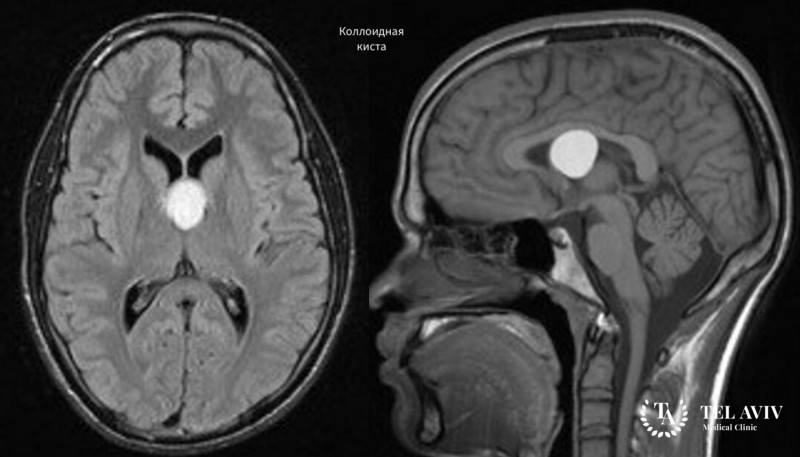

Предварительный диагноз ставится на основе клинической симптоматики. Для подтверждения диагноза могут назначаться визиометрия, офтальмоскопия, эхо-энцефалографии (определяет внутричерепное давление). Для визуализации кисты назначается УЗИ и МРТ.